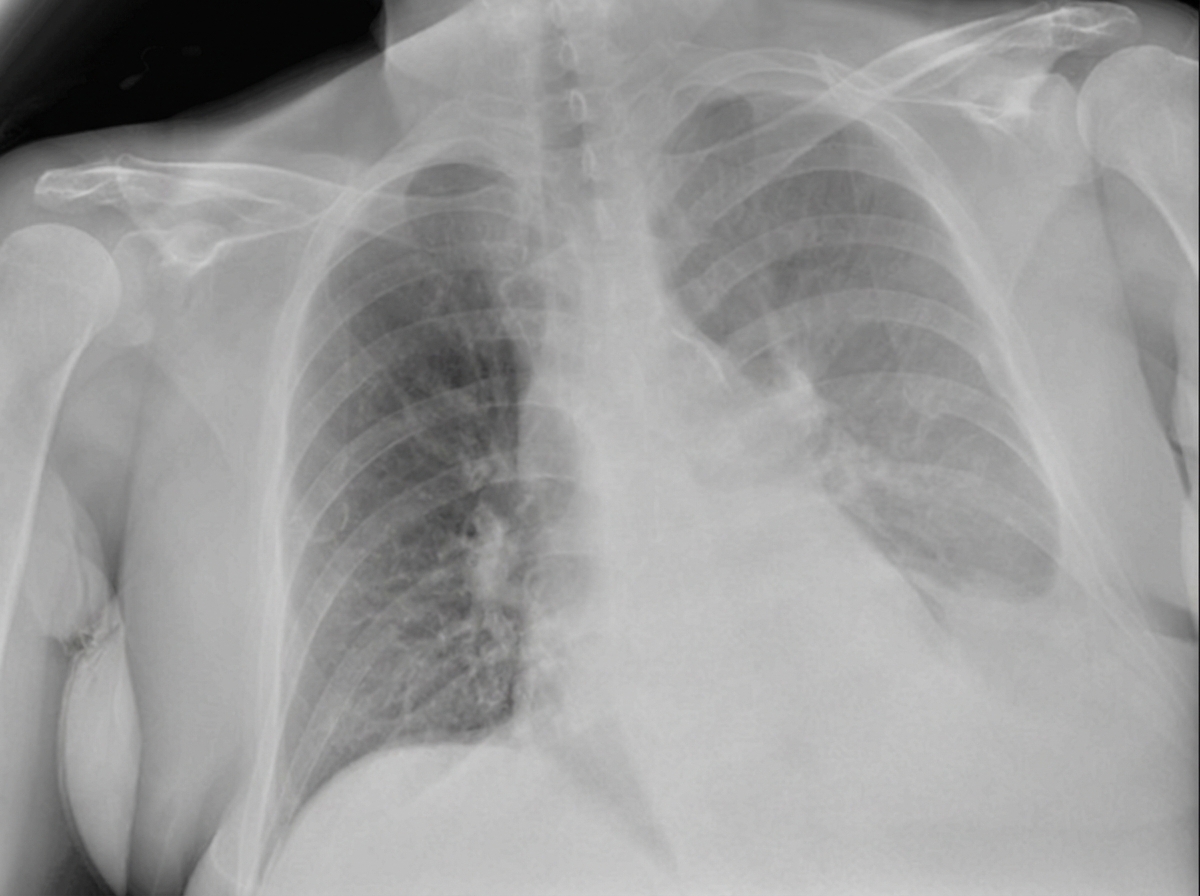

A 28-year-old woman is brought to the emergency department 30 minutes after being involved in a high-speed motor vehicle collision in which she was the unrestrained driver. On arrival, she is semiconscious and incoherent. She has shortness of breath and is cyanotic. Her pulse is 112/min, respirations are 59/min, and blood pressure is 128/89 mm Hg. Examination shows a 3-cm (1.2-in) laceration on the forehead and multiple abrasions over the thorax and abdomen. There is crepitation on palpation of the thorax on the right. Auscultation of the lung shows decreased breath sounds on the right side. A crunching sound synchronous with the heartbeat is heard best over the precordium. There is dullness on percussion of the right hemithorax. The lips and tongue have a bluish discoloration. There is an open femur fracture on the left. The remainder of the examination shows no abnormalities. Arterial blood gas analysis on room air shows: pH 7.31 PCO2 55 mm Hg PO2 42 mm Hg HCO3- 22 mEq/L O2 saturation 76% The patient is intubated and mechanically ventilated. Infusion of 0.9% saline is begun. Which of the following is the most likely diagnosis?

A 27-year-old soldier is brought to the emergency department of a military hospital 20 minutes after being involved in a motor vehicle accident during a training exercise. He was an unrestrained passenger. On arrival, he has shortness of breath and chest pain. He appears pale and anxious. His temperature is 37°C (98.6°F), pulse is 110/min, respirations are 20/min, and blood pressure is 100/65 mm Hg. He is alert and oriented to person, place, and time. Examination shows pale conjunctivae and mucous membranes. There is bruising on the chest, extremities, and abdomen. The lungs are clear to auscultation. He has normal heart sounds and flat neck veins. The abdomen is flat, soft, and mildly tender. The remainder of the physical examination shows no abnormalities. High-flow oxygen is applied, and intravenous fluid resuscitation is begun. A chest x-ray is obtained. Which of the following is the most appropriate next step in management?